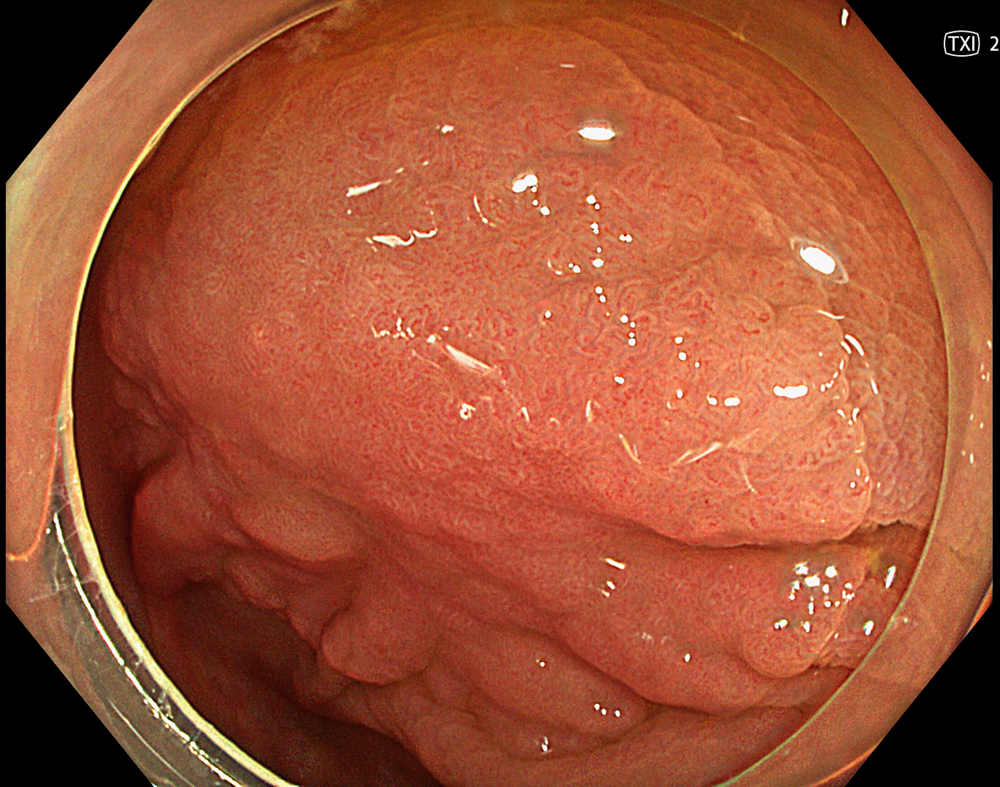

4. LST-NG in WLI

A 30-mm non-granular laterally spreading tumor (LST-NG-FE) located at the hepatic flexure is observed as a flat elevated lesion on white light imaging.

Enhancement : A8

NBI Mode : NA

TXI Mode : NA

RDI Mode : NA

BAI-MAC : On